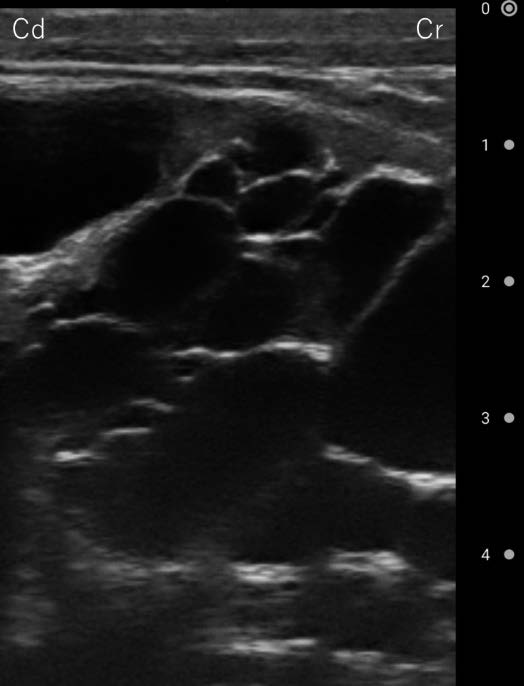

超音波検査:臍静脈の腫脹が認められ,さらに腹腔内の腫瘤については図1 のような像が得られた.

図1 腫瘤物の超音波画像(右腹壁)

Cr:頭側,Cd:尾側

水腎症では,腎盂がエコーフリー(黒色)の腫大した蜂の巣状像や菲薄した腎実質が描出される.また,尿路閉塞例では,管状のエコーフリーの拡張した尿管が描出される.